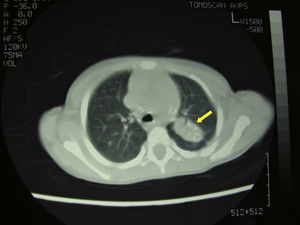

Dada la evolución tórpida, el origen de la paciente y los hallazgos radiológicos se amplió el estudio, realizándose Mantoux que resultó positivo (22mm) y radiografía de tórax en la que se observó consolidación en lóbulo pulmonar superior izquierdo. La TC torácica fue compatible con tuberculosis pulmonar (fig. 3). Se decidió realizar una artrotomía de cadera con limpieza de la zona y toma de muestras. En la tinción de Zhiel-Nielsen se objetivaron bacilos ácido alcohol ressitentes, iniciándose tratamiento con cuádruple terapia (isoniazida, rifampicina, pirazinamida y etambutol). Tras 2 semanas de tratamiento la paciente comenzó a apoyar la extremidad y transcurrido un mes volvió a caminar. Pasados 2 meses, la exploración articular era normal. El cultivo confirmó la presencia de Mycobacterium tuberculosis sensible a isoniazida y rifampicina por lo que, tras 2 meses de cuádruple terapia, se suspendieron el etambutol y la pirazinamida y se continuó tratamiento con dos fármacos durante 10 meses más.